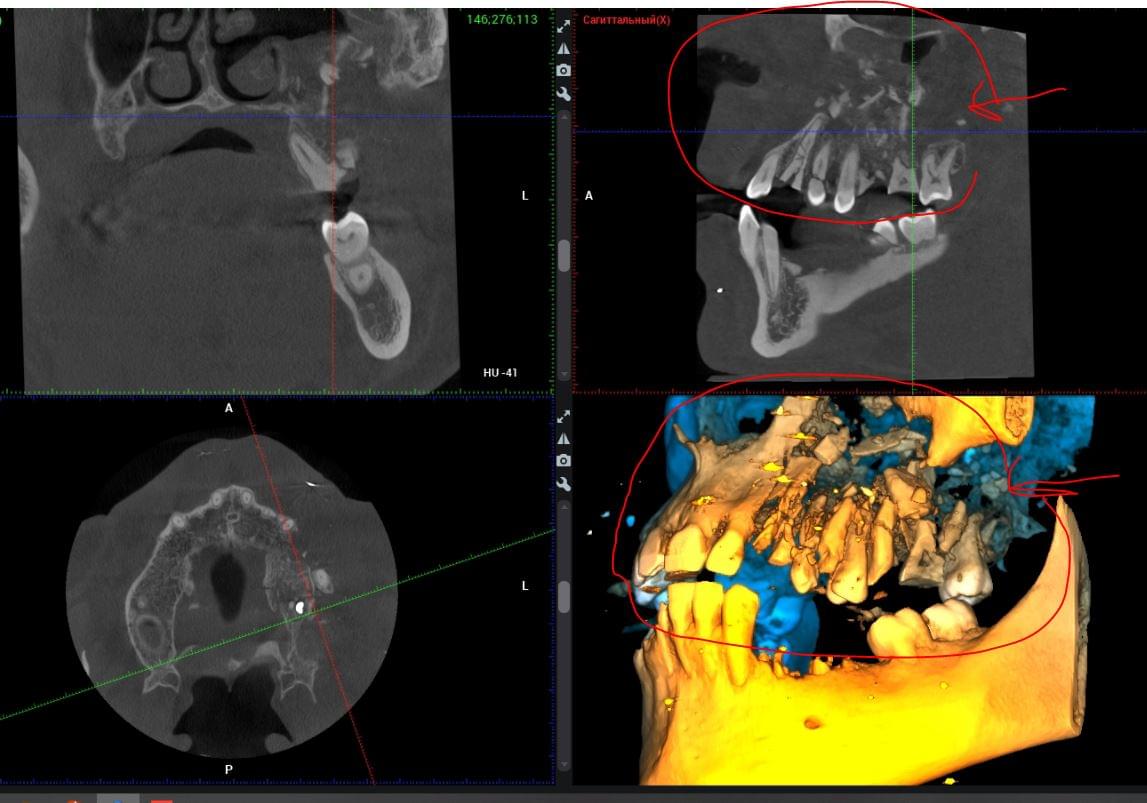

КПКТ (конусно-променева комп’ютерна томографія) — це 3D-знімок високої роздільної здатності. На відміну від звичайного рентгену, КТ показує:

КТ дозволяє провести віртуальну операцію: встановити імплант у програмі, виключивши будь-які ризики травмування пацієнта.